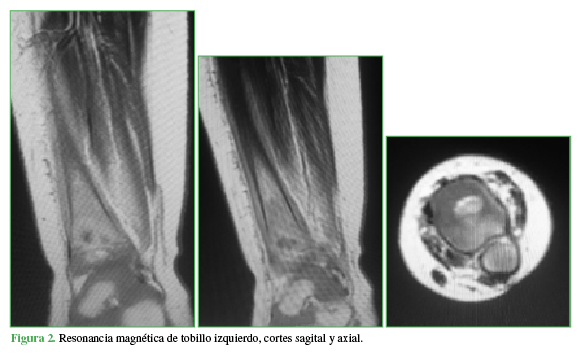

En la resonancia magnética de tobillo izquierdo bajo anestesia general, se observó una lesión bien definida, de 10 x 8 mm, a nivel diafiso-metafisario de la tibia distal izquierda, que comprometía cartílago de crecimiento con reacción esclerótica y edema medular óseo adyacente (Figura 2).